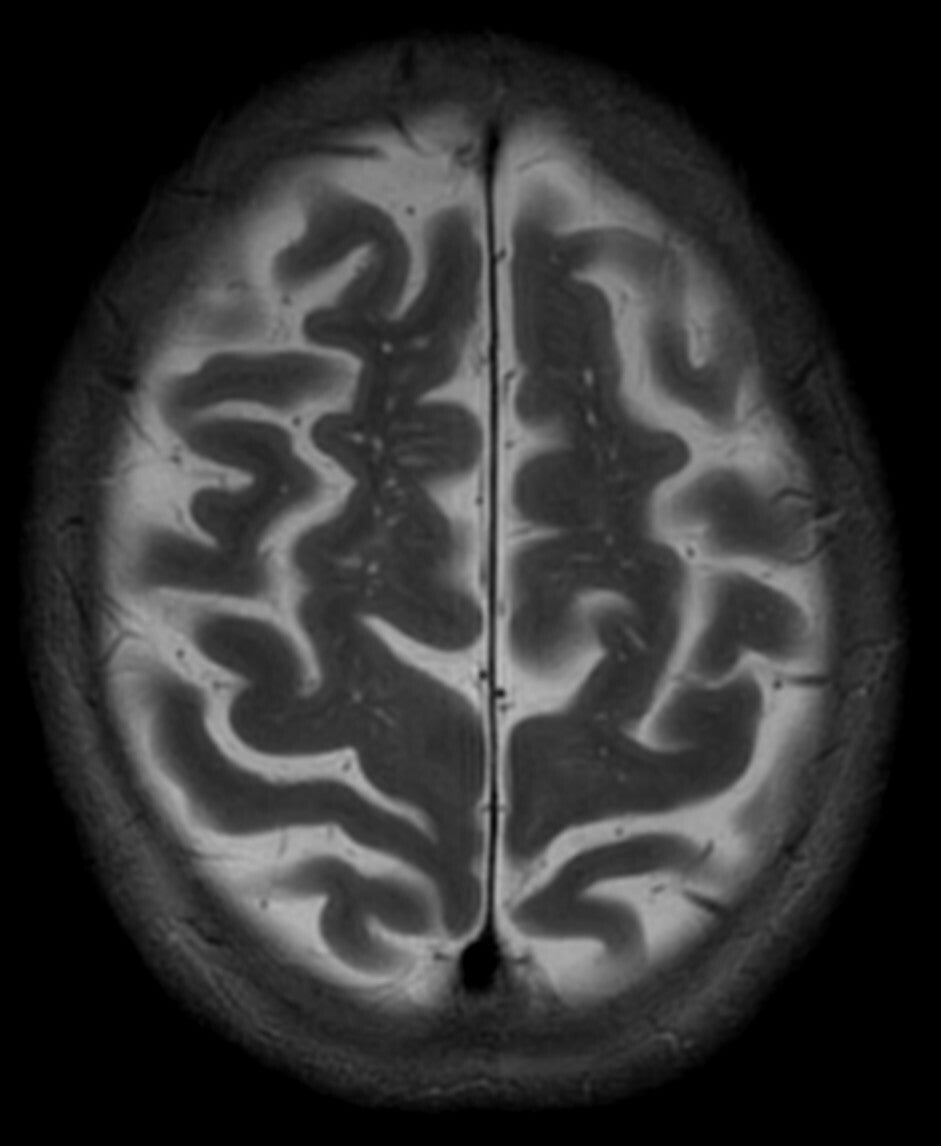

Characteristic appearances of 3 Tesla MRI imaging at a vault slice in a brain acquisition. In the first column, a picture of a microstarry sky in T1 acquisition is clearly evident and indicative of a miliary cysticercosis portrait, with multiple hollow cavities. In the second column, the corresponding snapshot in T2 is that of a myriad of point-like multiple dots, appearing as the hyperintense picture of the liquid inside the microcysts, being of the same liquor's density.

T1 (left)- and T2 (right)-weighed MRI appearance of distal cysticercal formations                     ST elevation of Prinzmetal angina